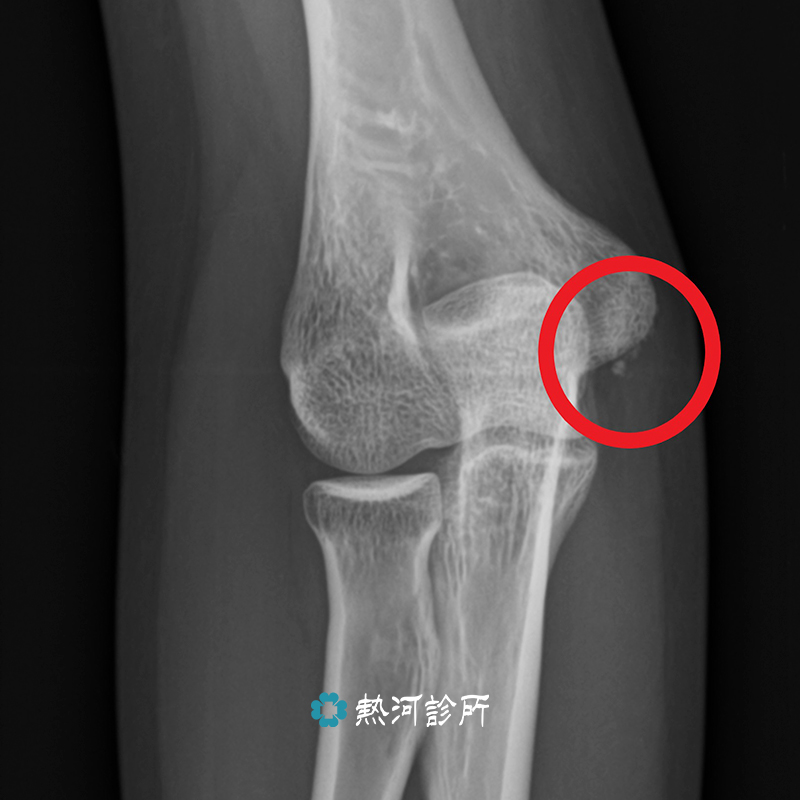

Jun 23, 2021 · 【健康醫療網/記者曾正豪報導】肘關節內上髁骨折是常見的肘部撕脫骨折,像是在平地跌倒、投擲等運動損傷都可能埋下危險因子。亞洲大學附屬.